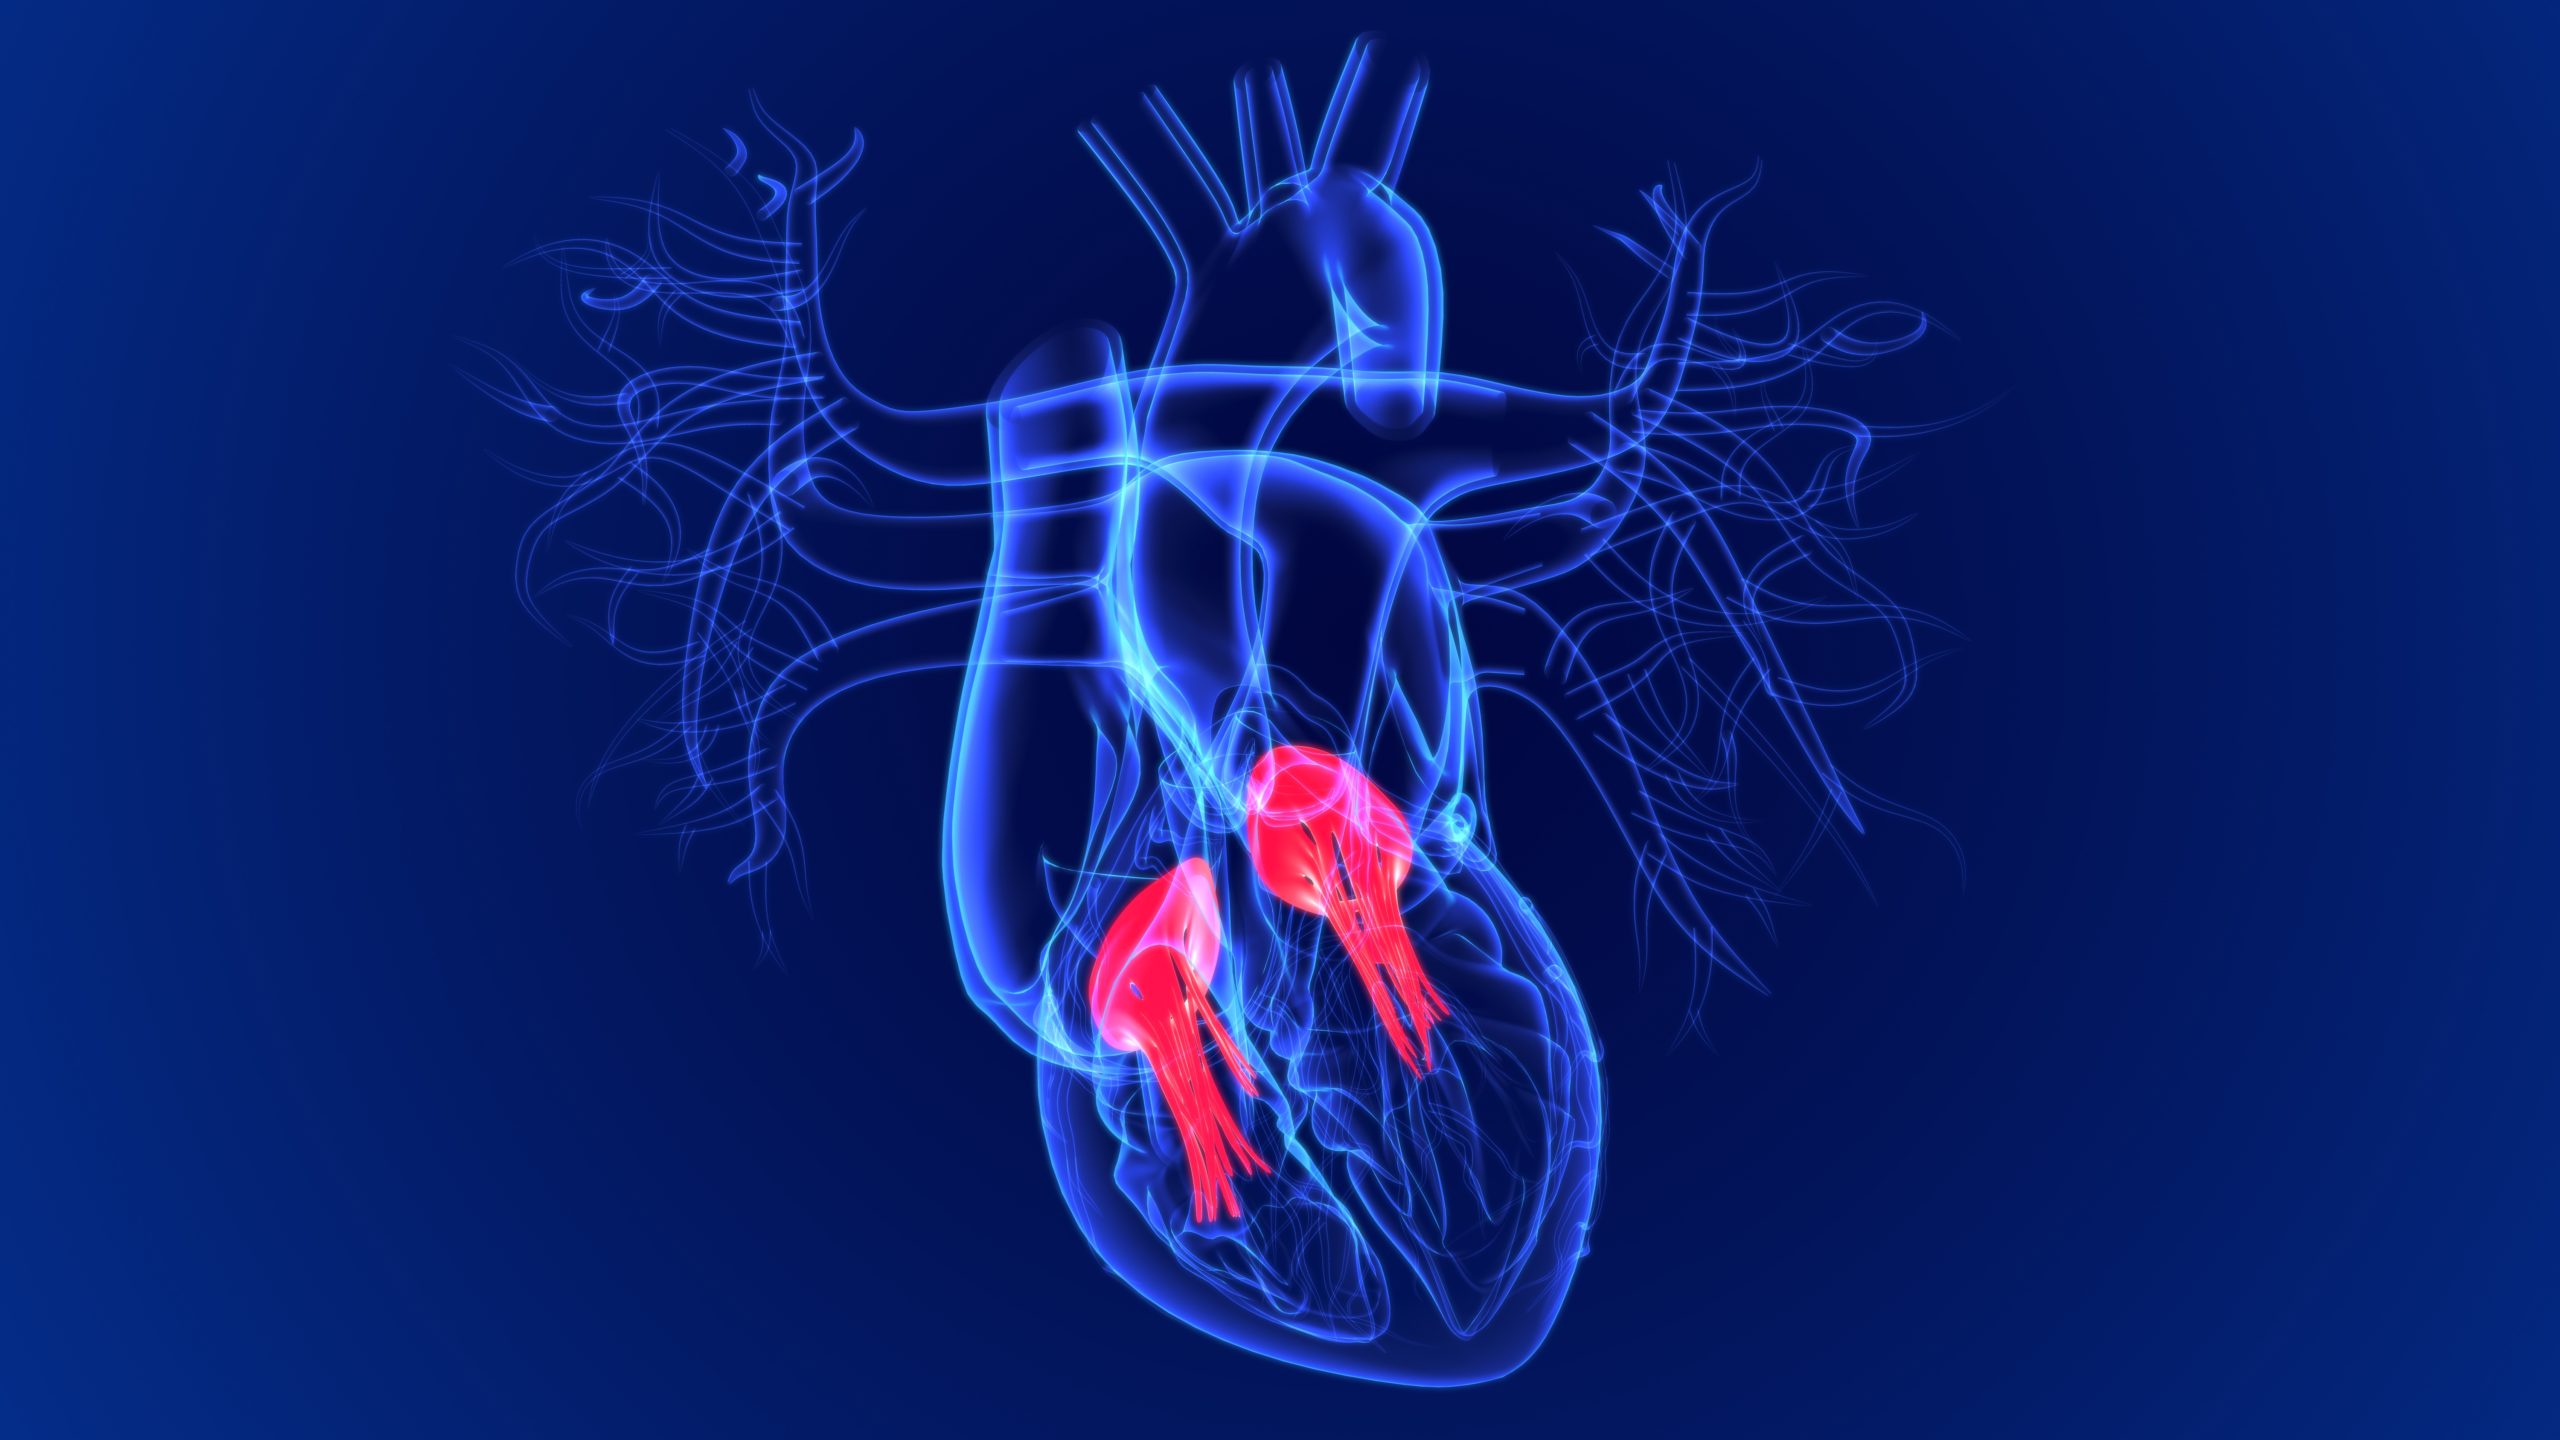

VALOR-HCM: Mavacamten Decreases Need for Septal Reduction Therapy in Symptomatic Obstructive HCM

Researchers, led by Ahmet Zengin, MD, from the Dr. Siyami Ersek Thoracic and Cardiovascular Surgery Center in ...

Many individuals who suffer sudden cardiac death (SCD) had previously experienced silent myocardial infarctions (SMIs), ...